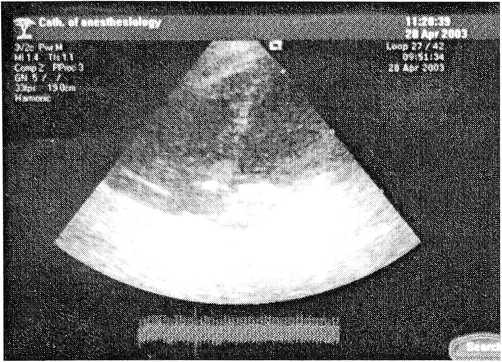

Наблюдение 5. Больная В. (история болезни 39774), 42 года, поступила на плановое оперативное лечение по поводу миомы матки 6/7 недель беременности, очагового аденоматоза эндометрия, цистаденомы левого яичника. Пациентке запланирована операция лапароскопия, гистерэктомия с придатками матки. Больной назначена профилактика ТЭО гепарином в соответствии с международными рекомендациями. Операция и ранний послеоперационный период протекали без осложнений. Длительность операции 2 ч 50 мин. Через 21 ч после операции после врачебного обхода больной произведена перевязка, удаление дренажа из ректоматочного пространства — без особенностей. Через 21 ч 50 мин после операции при вставании с постели больная пожаловалась на головокружение, далее произошла потеря сознания. При осмотре: сознание отсутствует, нарушения дыхания нет, пульс — 74 уд./мин, АД — 105/70 мм рт. ст. Также выявлен правосторонний гемипарез, горизонтальный нистагм с фиксацией взора вправо. Предположительный диагноз: острое нарушение мозгового кровообращения по ишемическому типу. Экстренная консультация невропатологом, люмбальная пункция (ликвор прозрачный, бесцветный). Установлен диагноз: острое нарушение мозгового кровообращения по ишемическому типу в левом каротидном бассейне. На каталке доставлена в отделение лучевой диагностики, где выполнена магнитно-резонансная томография головного мозга, на которой выявлены MP-признаки тромбоза левой внутренней сонной артерии (рис. 1).

Рис. 1. МРТ больной В. (прямая проекция).

В левой сонной артерии на всем протяжении отсутствует эффект «пустого потока» и ЛВСА имеет измененный МР- сигнал, что свидетельствует об отсутствии тока крови или тромбозе